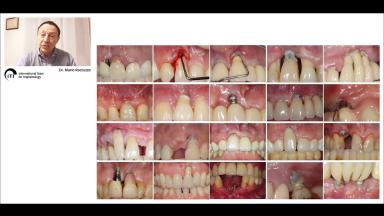

One of the greatest challenges facing clinicians is to obtain an early and long-standing effective mucosa seal, capable of biologically protecting the peri-implant structures. This is particularly difficult in compromised sites, due to trauma, atrophy, and/or periodontal disease. Recent systematic reviews have confirmed that the presence of an appropriate amount of keratinized mucosa is desirable.